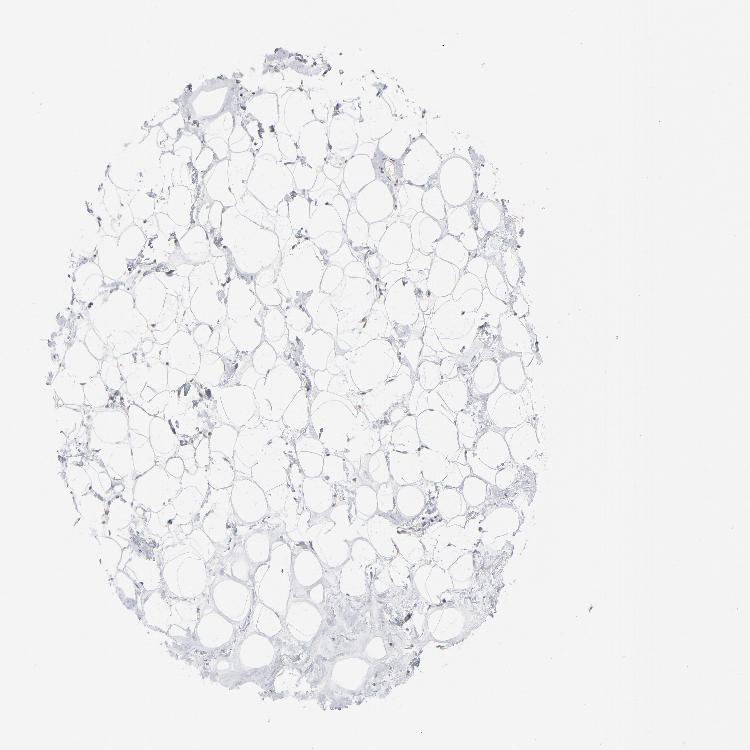

BREAST - Antibody stainingi

Antibody staining in the annotated cell types in the current human tissue is reported as not detected, low, medium, or high, based on conventional immunohistochemistry profiling in selected tissues. This score is based on the combination of the staining intensity and fraction of stained cells.

Each image is clickable and will lead to virtual microscopy that enables deeper exploration of all samples and also displays staining intensity scores, fraction scores and subcellular localization as well as patient and tissue information for each sample.

Antibody HPA003647

Adipocytes Not detected